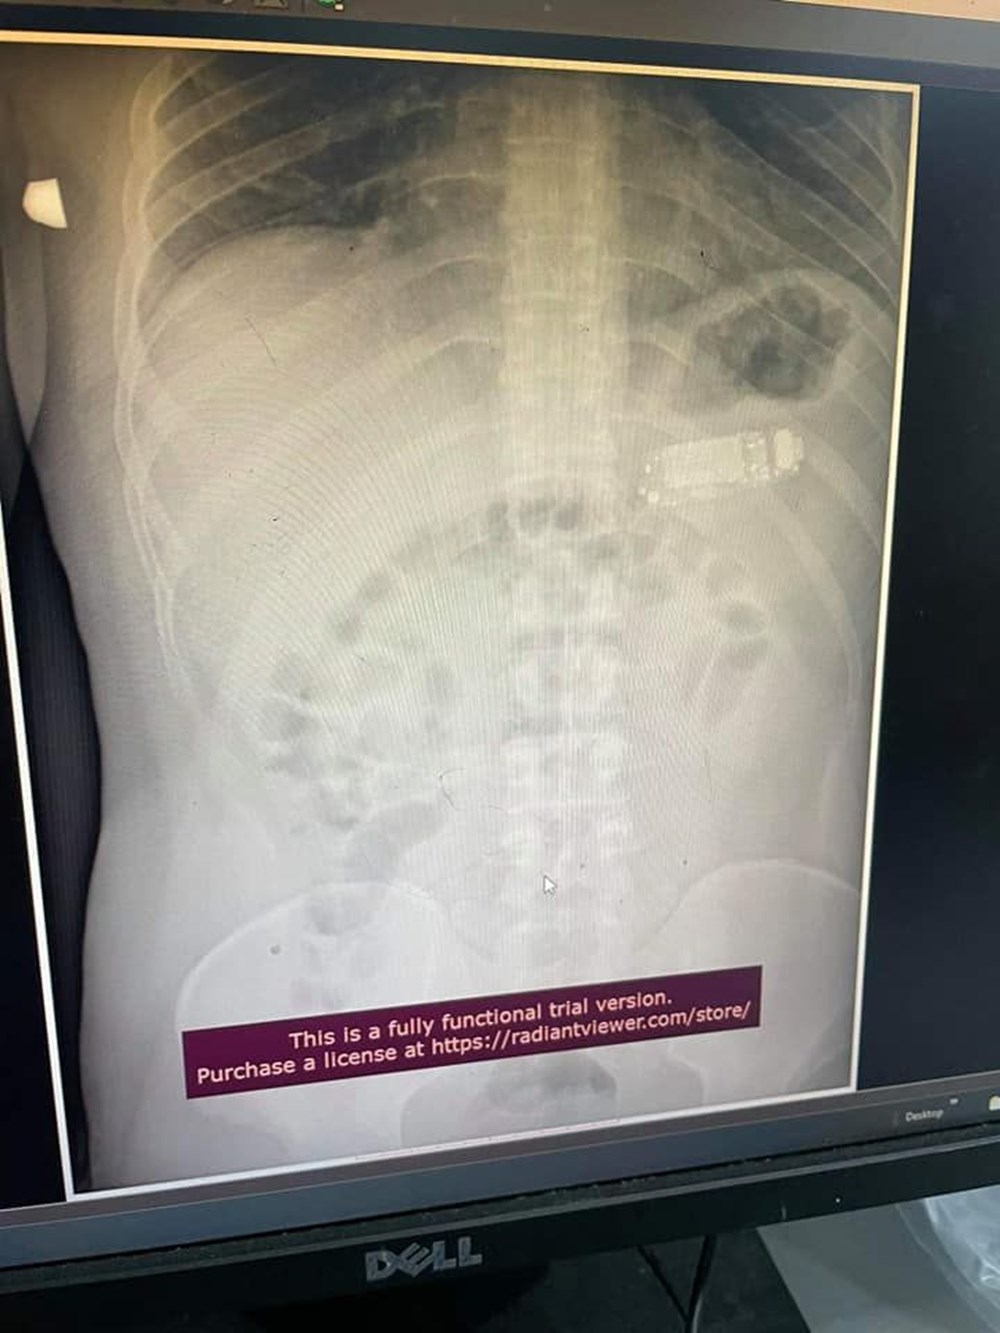

Operasyonu başarılı bir şekilde gerçekleştiren sağlık ekibinin başındaki doktor Skender Teljaku, adamın midesinden çıkarılan telefonun fotoğrafları ile röntgen ve endoskop görüntülerini Facebook'ta yayınladı.

Doktor Teljaku yaptığı açıklamada, tıbbi ekibin telefonu mideyi kesmeden, endoskop olarak bilinen özel cihazlar kullanarak üç ayrı parçaya ayırmayı başardığını belirtti. Teljaku, ayrıca yaklaşık iki saat süren işlem sırasında "herhangi bir komplikasyon" yaşanmadığını da vurguladı.